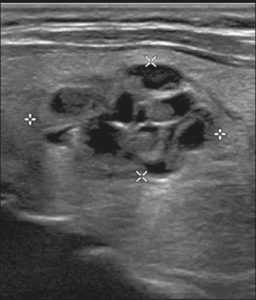

Hình 20. Hình ảnh nhân giáp hỗn hợp đặc và nang (1 điểm), đồng âm (1 điểm), rộng hơn cao (0 điểm), và lan rộng ra ngoài giới hạn phía trước của tuyến giáp (3 điểm), không có các ổ tăng âm hay bóng lưng (0 điểm). Do đó, tổng điểm là 5 điểm và mức độ nguy cơ được phân loại là TR4.